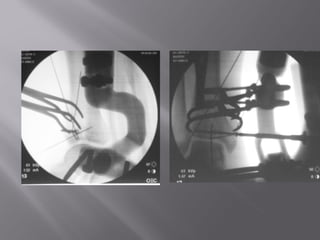

Percutaneous reduction sequence

visualized flouroscopically